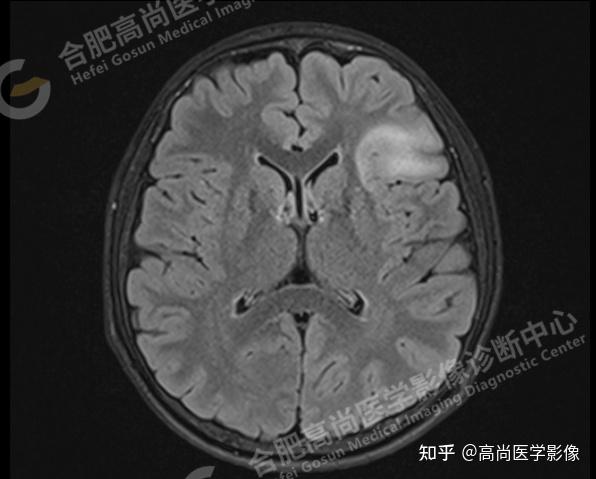

1 医学中MRS代表磁共振波谱,这是一种高分辨率的成像技术,基于核磁共振2 MRS能够检测人体内的代谢产物,如葡萄糖乳酸和肌酸,进而揭示人体的代谢状况3 在神经功能疾病和代谢疾病的研究中,MRS技术扮演着关键角色4 MRS能够识别肿瘤及其周围组织的代谢变化,这对肿瘤治疗和疗效评估具有重要指导意义5。